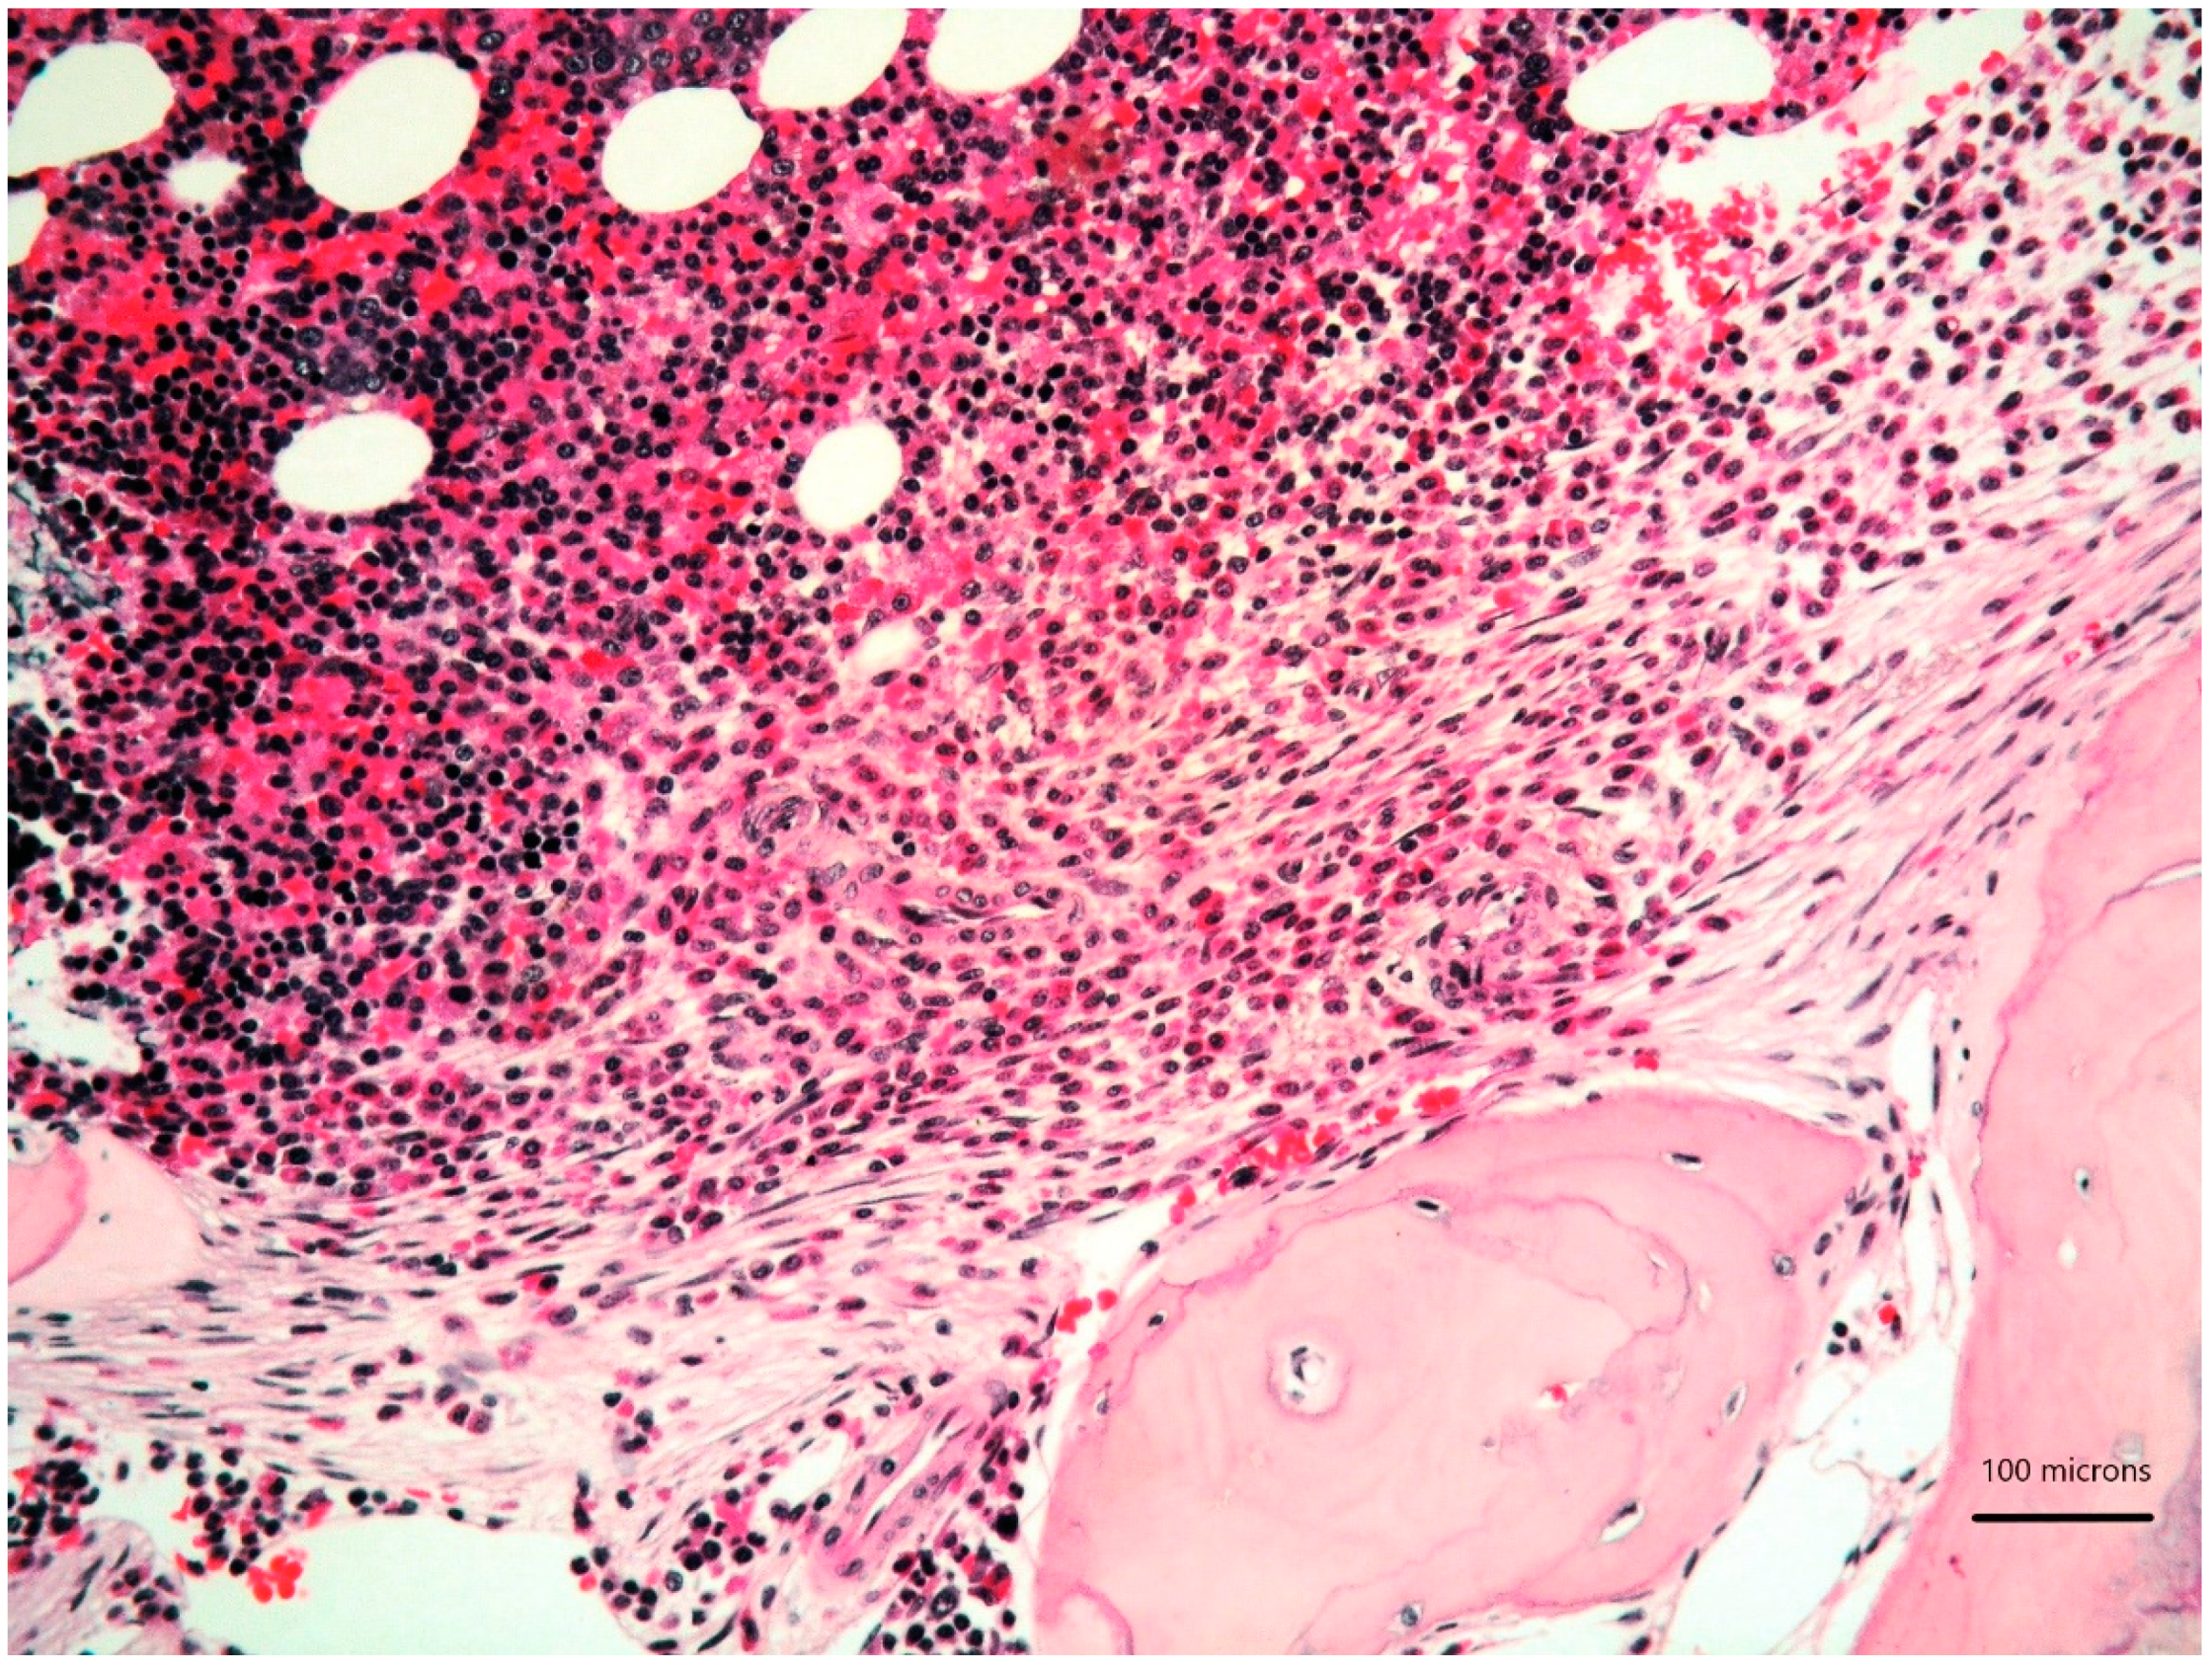

A 79-year-old woman was referred for a long history of peripheral eosinophilia. She underwent right hemicolectomy for colonic polyposis a few years before. Laboratory tests disclosed mild macrocitic anaemia (Hb 10.4 g/dL, MCV 93%) and eosinophilia (leukocytes 3360/mmc, eosinophils 30%). β2 microglobulin (3256 ng/dL; reference range 1010–1730) and serum tryptase (138 ng/L; reference range 0–11.4) were elevated. Serum immunofixation revealed IgA/kappa monoclonal protein (21 g/L). Bence-Jones protein was positive. Bone marrow (BM) biopsy revealed two neoplastic components. Low- and high-power views of haematoxylin and eosin sections showed cohesive paratrabecular aggregates of bland-looking, spindle-shaped cells (

Figure 1;

Figure 2 lower part) positive for CD117 (

Figure 3), tryptase and CD25 representing 20% of marrow cellularity. Aggregates of mature plasma cells (

Figure 1;

Figure 2 upper part) positive for CD138 (

Figure 4), MUM1/IRF4 and kappa light chain occupied 40% of the remaining bone marrow. Bone marrow aspirate confirmed the presence of the two neoplastic components (

Figure 5). KITD816V mutation was detected by DHPLC and confirmed by Sanger sequencing; TET2 mutation was identified using DNA sequence analysis on marrow aspirate. Monoallelic deletion of TP53/17p13 and trisomy of ATM/11q23 was detected by FISH analysis on BM enriched with plasma cells using CD138+ magnetic Micro-Beads, respectively, in 39% and 94% of nuclei. RUNX1, ASXL1, SRSF2 and U2AF1 were unmutated. Osteoporosis was identified by full skeletal X-rays and MRI. The case was referred to as SM with concomitant smoldering MM.

The diagnosis of SM was proposed owing to the fulfilment of the major diagnostic criteria (multifocal, dense, compact aggregates in bone marrow and/or extra-cutaneous organs) and three of the minor criteria (KIT D816V mutation, CD25 expression, serum tryptase level exceeding 20 ng/mL) combined with the presence of a C finding (organ involvement with loss of function: intestinal mastocytosis with clinical malabsorption identified in the previous colectomy specimen) [

1]. Due to the bone marrow findings, along with the absence of myeloma-defining events (frank anaemia, hypercalcemia, lytic bone lesions, renal insufficiency secondary to myeloma, recurrent bacterial infections, blood hyperviscosity, paraneoplastic neuropathy, signs of associated amyloidosis, spinal osseous lesions at MRI), our patient fitted into the diagnosis of smoldering MM.